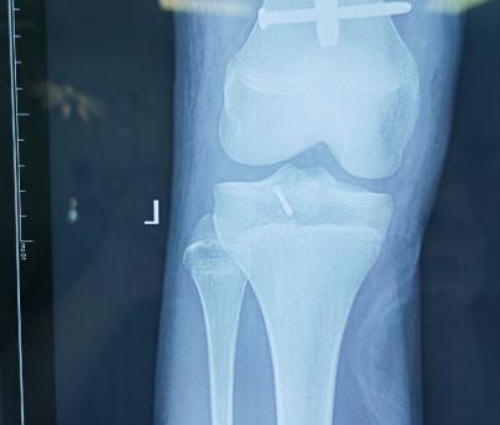

术后X光片

综合考虑后,刘万林教授团队为患者制定了应用骨科手术机器人辅助下进行手术的诊疗方案。通过机器人进行数据采集、手术规划等人工智能手段,术中仅用约2cm切口即成功完成手术。与传统手术相比,该手术切口明显减小,出血量少,达到了微创、精准、智能的手术效果,患者及家属非常满意。